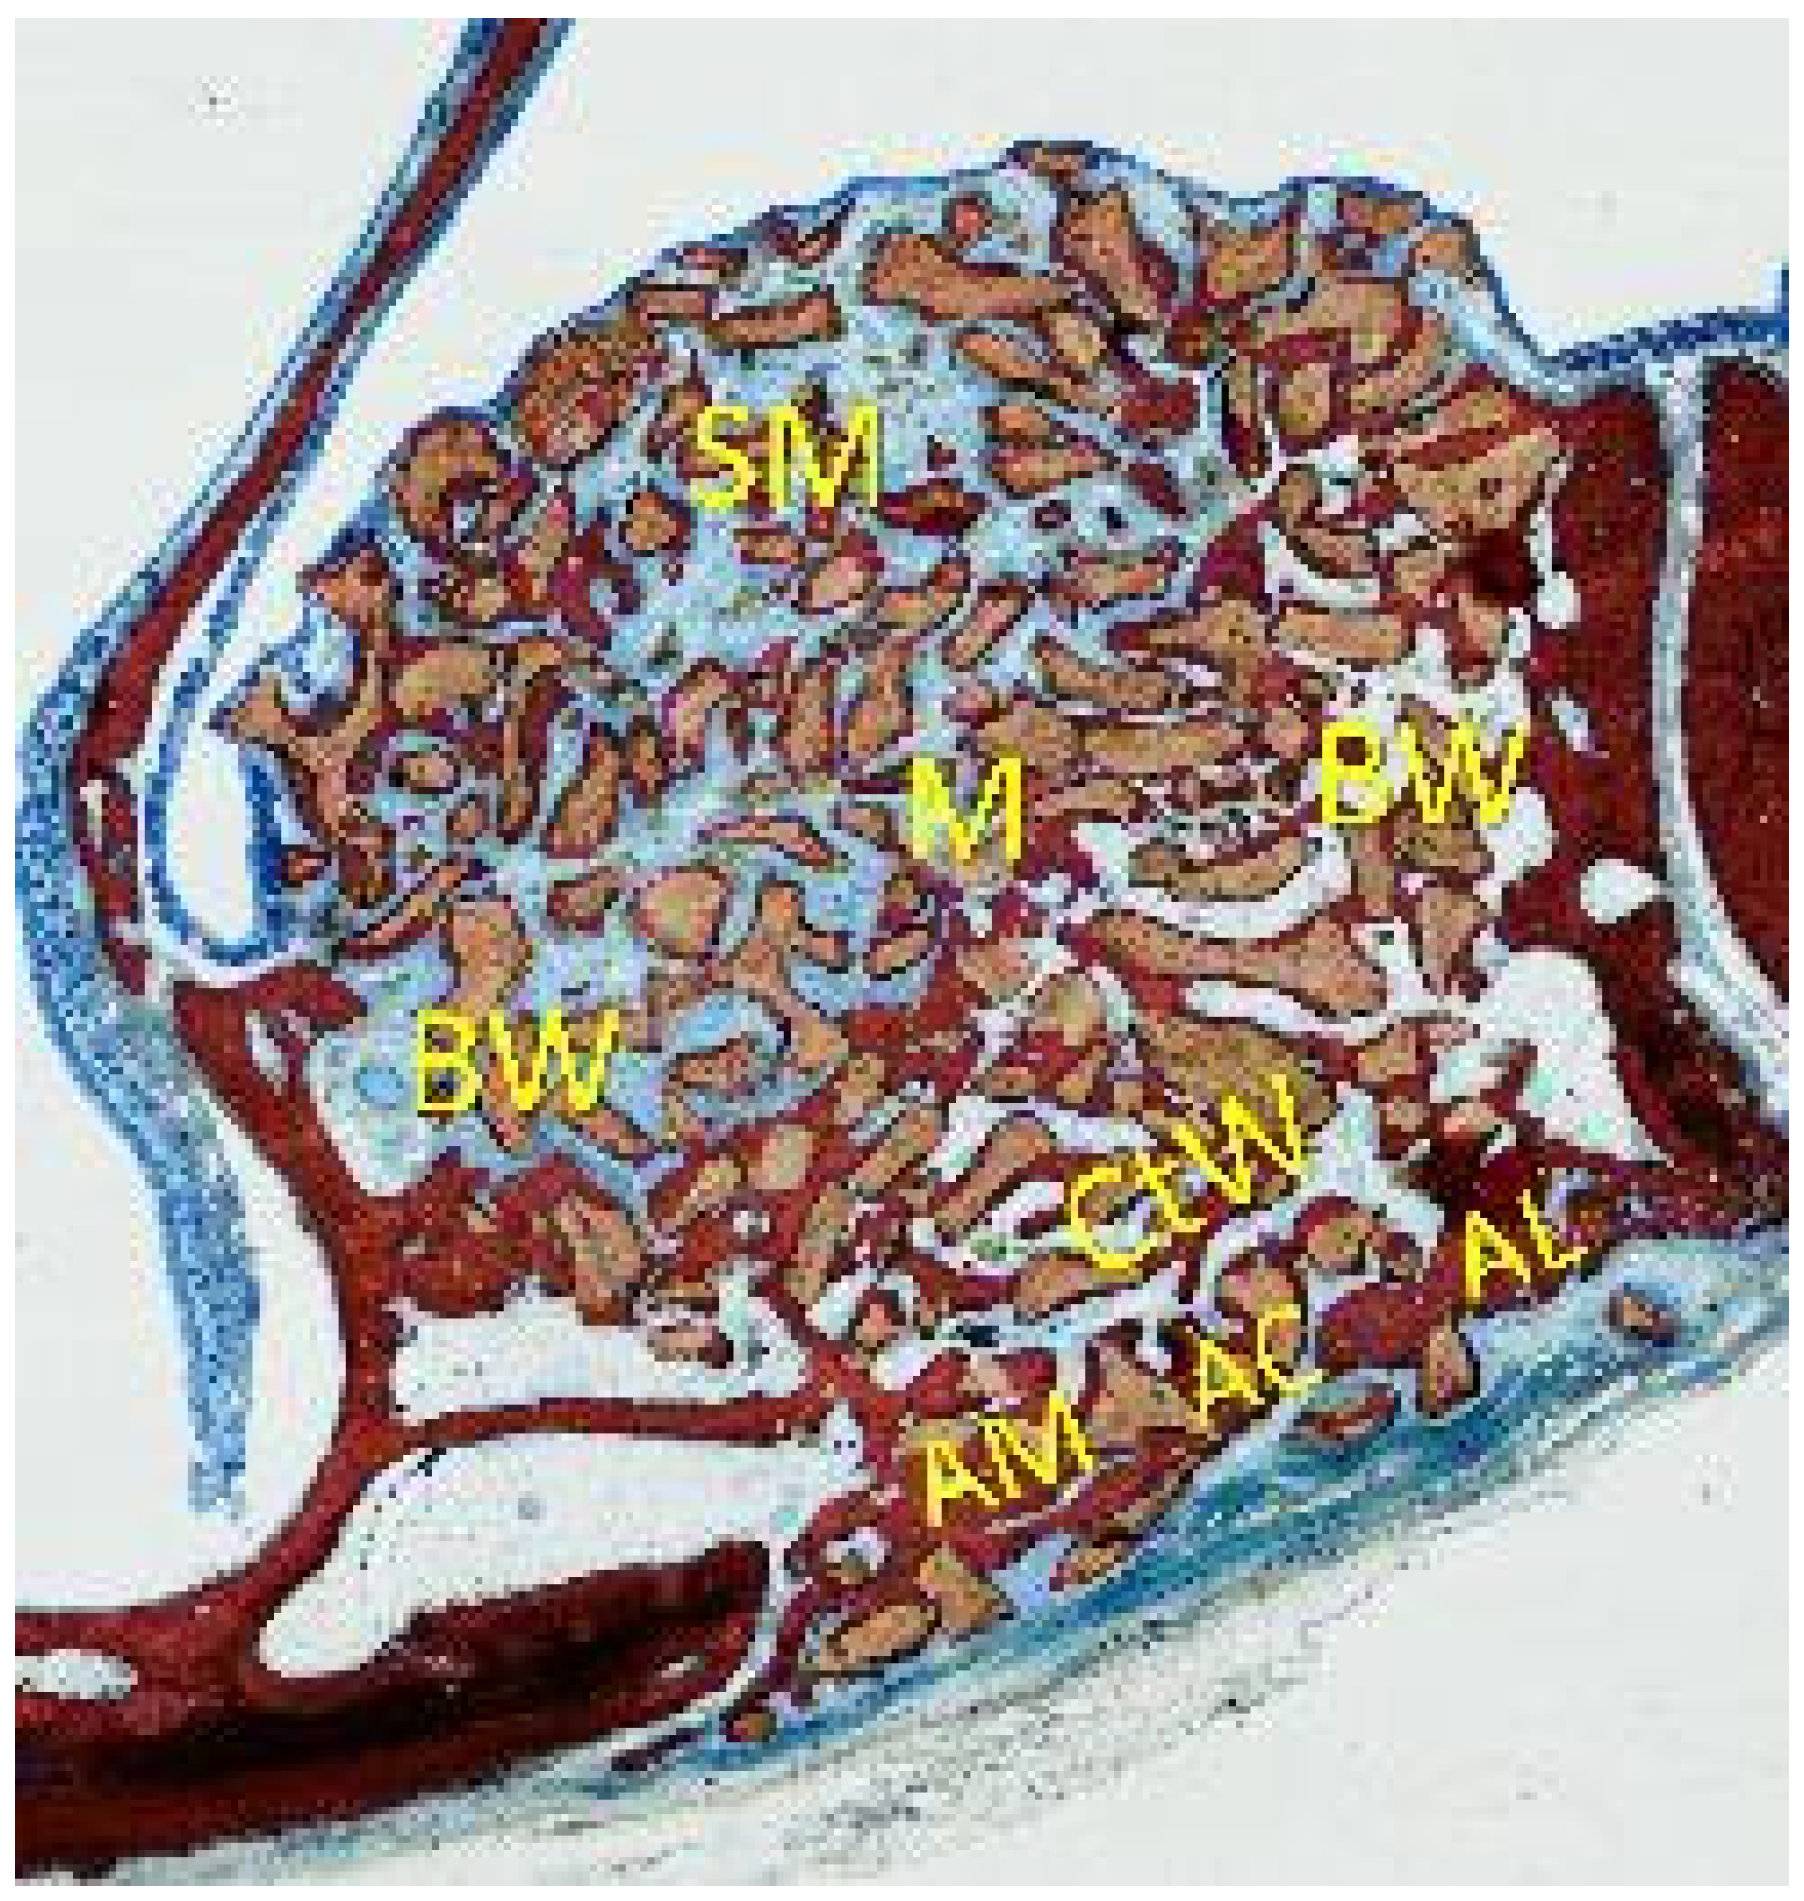

2.5. MicroCT Evaluations